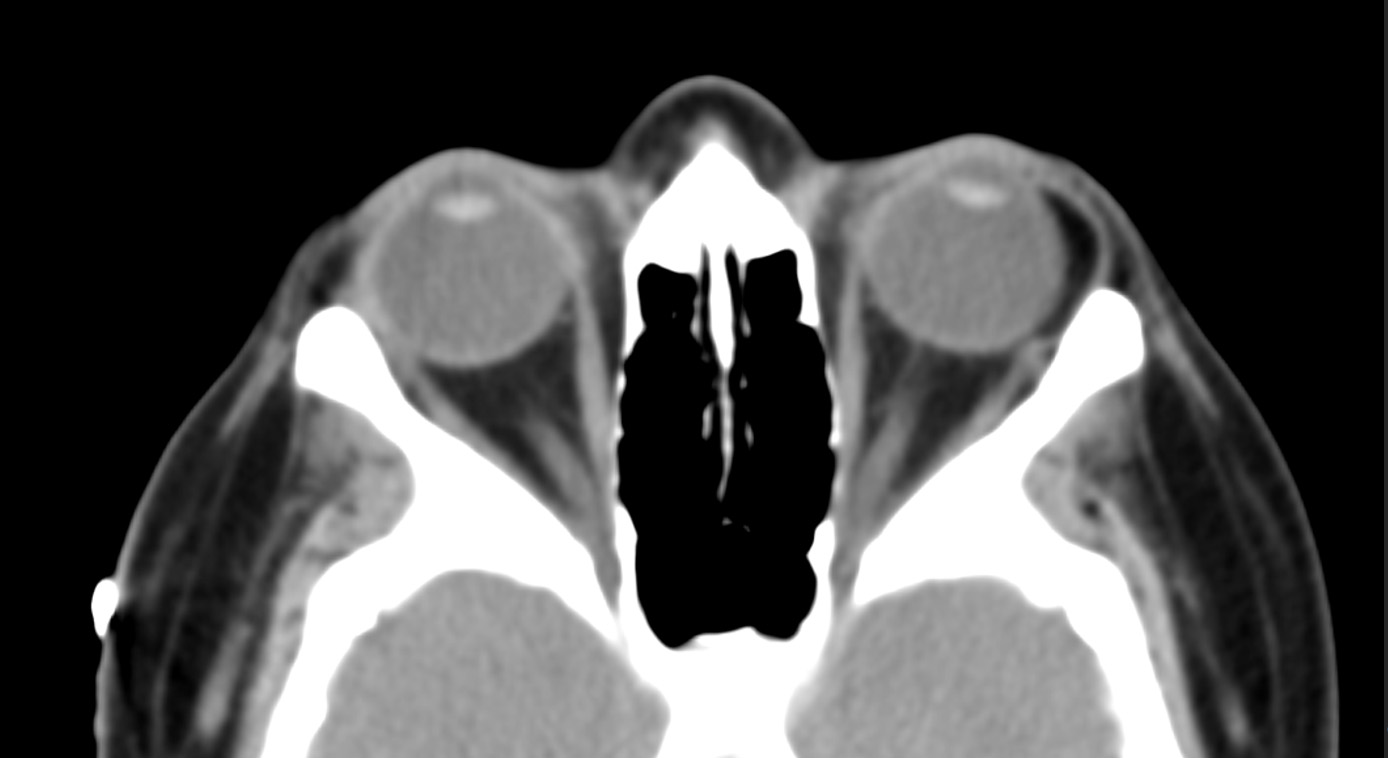

• Unilateral, crescent- or triangle-shaped fatty mass located at the temporal epibulbar area along lateral aspect of globe, anterior to insertion of lateral rectus muscle and medial to lacrimal gland (Figure 4) (Kim, Am J Neuroradiol, 2011)

• No radiographic evidence of connection to intraconal fat, in contrast to orbital fat prolapse

• Typically identical attenuation on CT or signal intensity on MRI compared to intraconal fat, though may display subtle soft tissue stranding on CT

Figure 4. Axial CT showing a dermolipoma on the left

(Radiographic image made available by Dr. Edward Kuoy, Department of Radiology, University of California, Irvine)